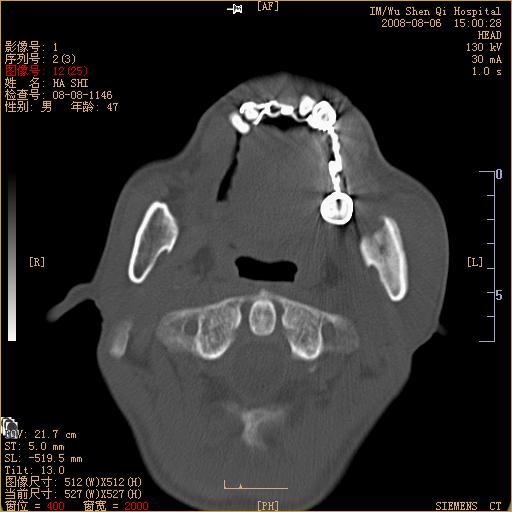

标题: CT15051:男 47岁 左下颌角部肿痛一周 [打印本页]

标题: CT15051:男 47岁 左下颌角部肿痛一周

骨质破坏,无硬化边,周围软组织肿胀,占位

左下颌骨感染性病变,牙源性可能。

左侧下颌智齿阻生。

考虑左下颌骨骨髓炎。